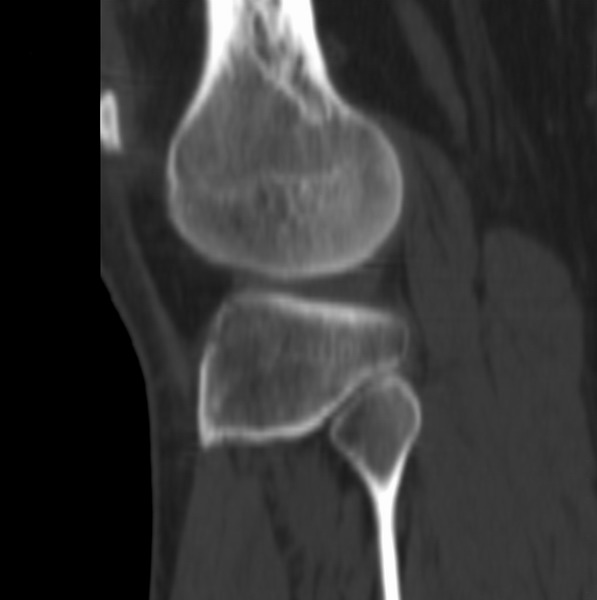

右侧膝关节疼痛一月

男、48

股骨下段、胫骨上段。

1、股骨干骺端病变考虑干骺端纤维性皮质缺损愈后(非骨化性纤维瘤)改变,胫骨近端内生骨瘤(或干骺端纤维性皮质缺损愈后改变);

2、骨关节炎,骨质增生,股骨外侧髁退变性囊肿(关节面软骨下囊肿);

3、髌骨前缘裂纹骨折?